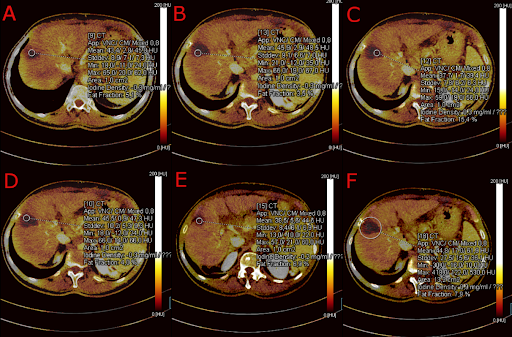

E' stata adoperata sempre la stessa macchina dotata di detettori a 128 strati (TC SOMATOM Definition Edge di Siemens Healthcare, Erlangen, Germania) con una risoluzione spaziale di 0,30 mm, dotata di tecnologia Twin-Beam. L'analisi delle immagini a doppia energia è stata eseguito tramite il software syngoCT Workplace VB20 di Siemens Healthcare GmbH (Erlangen, Germania) con l’applicativo “Liver VNC Application Class” per l'analisi delle scansioni TC eseguite in fase portale TBDE. Sulle immagini VNC, un radiologo esperto ha tracciato da 3 a 6 regions of interest (ROI) per ciascuna lesione (superiore, inferiore ed in base all'estensione da 1 a 4 ROI centrali) con area di 1 cm^2, una ROI centrale più estesa che comprendesse 5 mm di parenchima epatico non-ablato tracciato sullo stesso piano della ROI centrale di 1 cm^2 (FIGURA 2-3-4-5). Nel tracciare le ROI si è posta la massima attenzione nell’evitare strutture peri-lesionali e i vasi sanguigni. Per ogni ROI tracciata è stato estrapolato il valore quantitativo della densità dello iodio in mg/dl considerando anche valori negativi (ovvero privi di impregnazione di mezzo di contrasto). Allo stesso radiologo è stato poi richiesto di compilare in cieco, una scheda qualitativa che decretasse se il trattamento effettuato fosse "completo" o "incompleto" nelle TC analizzate (TABELLA 1).

FIGURA 5. Esempio di analisi VNC con mappa dello iodio. Sono visibili le ROI di 1 cm2 tracciate manualmente sul piano assiale con i rispettivi valori ottenuti. Rispettivamente: la ROI superiore (A), tre ROI sul piano centrale (B-C-D), la ROI inferiore (E) e la ROI centrale con incluso un bordo di parenchima di 5mm (F).